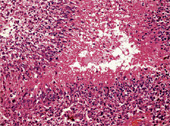

<p>In a collaborative research programme, scientists at the Indian Institute of Science (IISc) led by Professor Kumar Somasundaram, Department of Microbiology and Cell Biology (MCB), and Professor Vani Santosh from the National Institute of Mental Health and Neurosciences (NIMHANS), Bangalore, are using state of the art genetic engineering tools to precisely grade glioma, which is the most common primary tumour occurring in the human brain. </p>.<p>Haphazard division of cells<br /><br />Cancer is a group of diseases characterised by uncontrolled growth and spread of abnormal cells. We all know cells are the structural units of all living things. <br /><br />Each of us has trillions of cells and these cells make it possible for us to carry out all kinds of functions of life: the beating of the heart, breathing, digesting food, thinking, walking, and so on. The most fundamental characteristic of cells is their ability to reproduce themselves. They do this simply by dividing. One cell becomes two; the two become four, and so on. The division of normal and healthy cells occurs in a regulated and systematic fashion. In contrast, cancer cells divide in a haphazard manner. The result is that they typically pile up into a non-structured mass or tumour. <br /><br />Researchers are working hard to understand more about how genes work inside the body and why things sometimes go wrong. Recently, cancer research has focused on understanding how a normal cell, through a series of genetic changes, turns into a cancerous cell. A number of genes have been identified that play a part in the development of some cancers. If a person is born with a gene change (mutation) that makes them more likely to develop cancer, we say that they have inherited a cancer gene.<br /><br />Astrocytomas (the most commonly occurring glioma) are graded on a scale of I to IV according to their degree of malignancy as judged by various histological features. In order to help doctors grade astrocytomas, Somasundaram and his students are studying the “microRNA (miRNA) gene expression” for normal brain tissues and for grades III and IV astrocytoma, in order to identify a ‘miRNA expression signature’, which will help clinical investigators grade the tumours accurately. miRNAs are a class of small noncoding RNAs that control gene expression by targeting mRNAs. Aberrant expression of miRNAs may be involved in human diseases, including cancer.</p>.<p>Signature pattern<br /><br />In path-breaking research soon to be published, they have identified 24 miRNA genes from amongst several hundred that could be the ‘signature pattern’ for tumour grading. He says, “We have performed large-scale gene expression analysis on gliomas of all histology types to assess whether a gene expression-based, histology-independent classifier can be used by clinical investigators”. <br /><br />Results show that miRNA gene expression-based grouping of tumours is a powerful method of glioma grading. In experimental results, they have reported 95 percent accuracy in grading type III and IV astrocytomas. Brain tissue samples for this investigation were taken from patients who underwent surgery at NIMHANS. <br /><br />Prof Somasundaram says “with the advent of the molecular era, we now have the opportunity to re-examine the biology of these tumours with a level of precision that promises to make meaningful advances toward the development of specific and effective rational therapies”. <br /><br />Current glioma treatment involve a combination of – surgical intervention, radiation and chemotherapy, depending on the grade of the tumour.<br /><br />Neurosurgeons, clinical investigators and scientists working together on this research programme, feel that since accurate histopathological grading is not possible in all cases of glioma in view of limited sample size in many tumours, patients may be denied of appropriate treatment protocols. This however can be minimised by such robust technologies. <br /><br />They feel that the list of 24 miRNAs identified by them, are outstanding candidates for use in histology-independent classification of high-grade gliomas. <br />It is needless to say that additional validation on large set of samples is the immediate priority. </p>